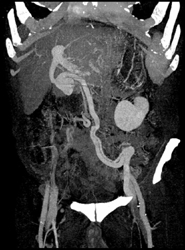

Pseudolesion of Liver